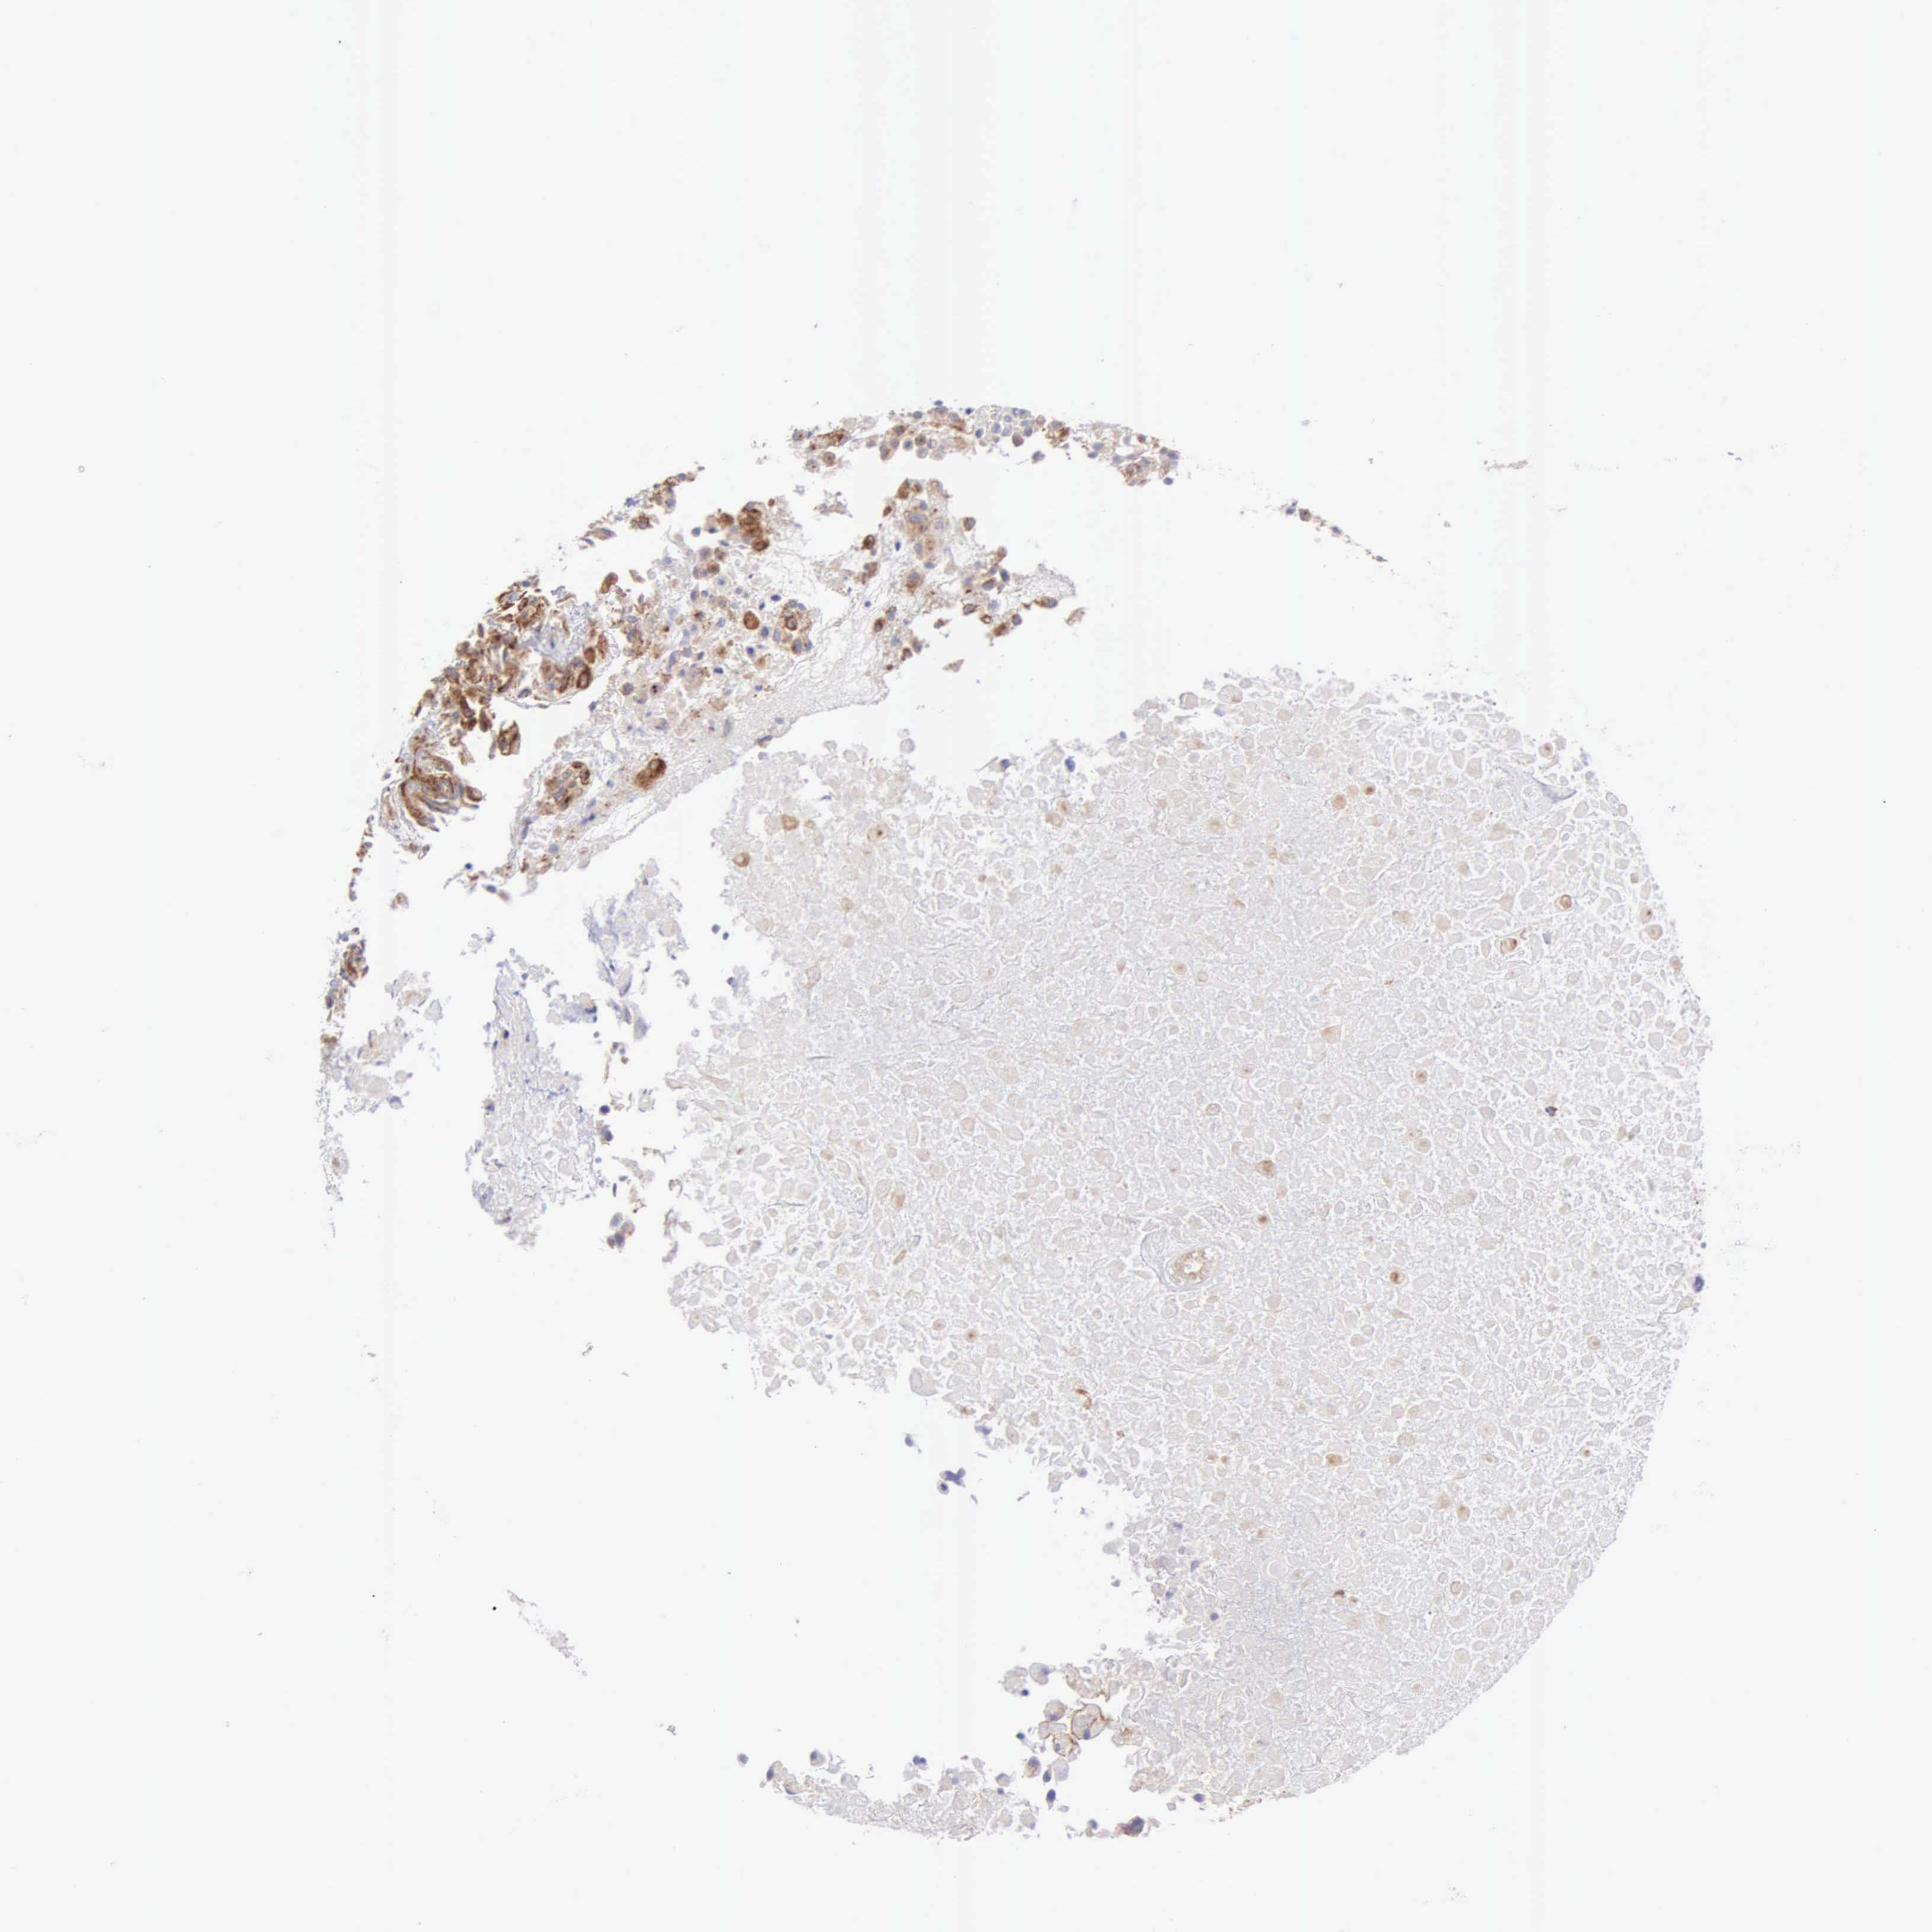

UROTHELIAL CANCER - Protein expressioni

A mouse-over function shows sample information and annotation data. Click on an image to view it in a full screen mode. Samples can be filtered based on level of antibody staining by selecting one or several of the following categories: high, medium, low and not detected. The assay and annotation is described here.

Note that samples used for immunohistochemistry by the Human Protein Atlas do not correspond to samples in the TCGA dataset.

Antibody stainingi

Antibody staining in the annotated cell types in the current human tissue is reported as not detected, low, medium, or high, based on conventional immunohistochemistry profiling in selected tissues. This score is based on the combination of the staining intensity and fraction of stained cells.

Each image is clickable and will lead to virtual microscopy that enables deeper exploration of all samples and also displays staining intensity scores, fraction scores and subcellular localization as well as patient and tissue information for each sample.

Antibody HPA001462

Antibody CAB000157

Staining

High

Medium

Low

Not detected

Intensity

Strong

Moderate

Weak

Negative

Quantity

>75%

75%-25%

<25%

None

Location

Nuclear

Cytoplasmic/membranous

Cytoplasmic/membranous,nuclear

Urothelial carcinoma, High grade

Urothelial carcinoma, Low grade

Adenocarcinoma, NOS